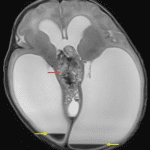

- Large, heterogeneous mass centered in the quadrigeminal plate region measuring 6 x 2.8 x 6 cm

- Extensive corresponding mass effect on the midbrain with effacement of the cerebral aqueduct and associated severe obstructive hydrocephalus with cerebral parenchymal thinning

- Small volume hemorrhage layering in both lateral ventricles and fourth ventricle with rounded clot in the third ventricle

- Small volume scattered subarachnoid hemorrhage

- The above described masses demonstrate areas of restricted diffusion (particularly the two smaller lesions) but no discrete enhancement